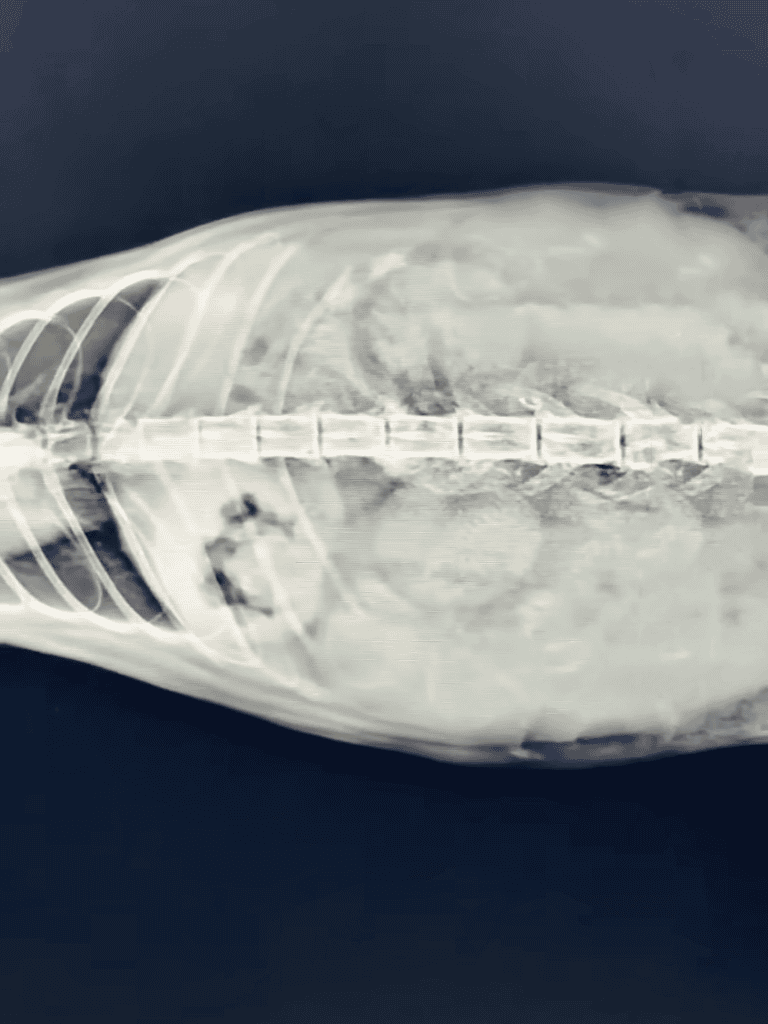

A scan revealed unborn kittens, two of which had weak heartbeats.

Once the cat was under anesthesia, the vet began a detailed examination and found evidence of canine bite marks alongside a myriad of old scars etched across her frail body.

A CT scan showed the cat was expecting, with kittens almost ready for their entrance into the world. However,

As the vet examined the fragile kittens, their faint heartbeats echoed the uncertainty of their survival. A race against time began, with immediate surgery standing as the only hope to save their fragile lives.